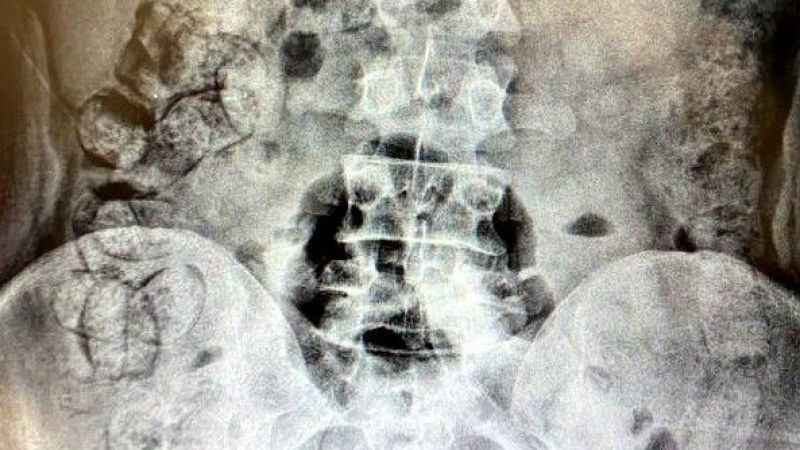

Erzincan Emniyet Müdürlüğü Narkotik Suçlarla Mücadele Şube Müdürlüğü ve KOM şube ekiplerince geçtiğimiz 28 Mart 2023 günü İran plakalı yolcu otobüsü uygulama noktasında durduruldu. Otobüste yolcu olarak bulunan Khadijah S., ve Samira T., isimli şahıslar ile aynı otobüste bağlantılı oldukları tespit edilen Allahniaz S., Raheleh Y., isimli İran uyruklu 4 şahsın yapılan iç beden muayenelerinde, yutma suretiyle uyuşturucu kuryeliği yaptıkları belirlendi. Şüpheli Khadijah S., isimli şahıstan 31 parça halinde yaklaşık ağırlığı 252,52 gram Afyon sakızı, Samira T., isimli şahıstan 64 parça halinde 440,78 gram, toplam 693,3 gram Afyon sakızı ele geçirildi.

Gözaltına alınan 1’i erkek 3’ü kadın 4 kişi emniyetteki sorgularının ardından uyuşturucu madde ticareti yapmak suçundan adliyeye sevk edildi. Adliyede Allahniaz A., adli kontrol şartıyla serbest kalırken Khadijah S., Samira T., ve Raheleh Y., tutuklanarak cezaevine gönderildi.